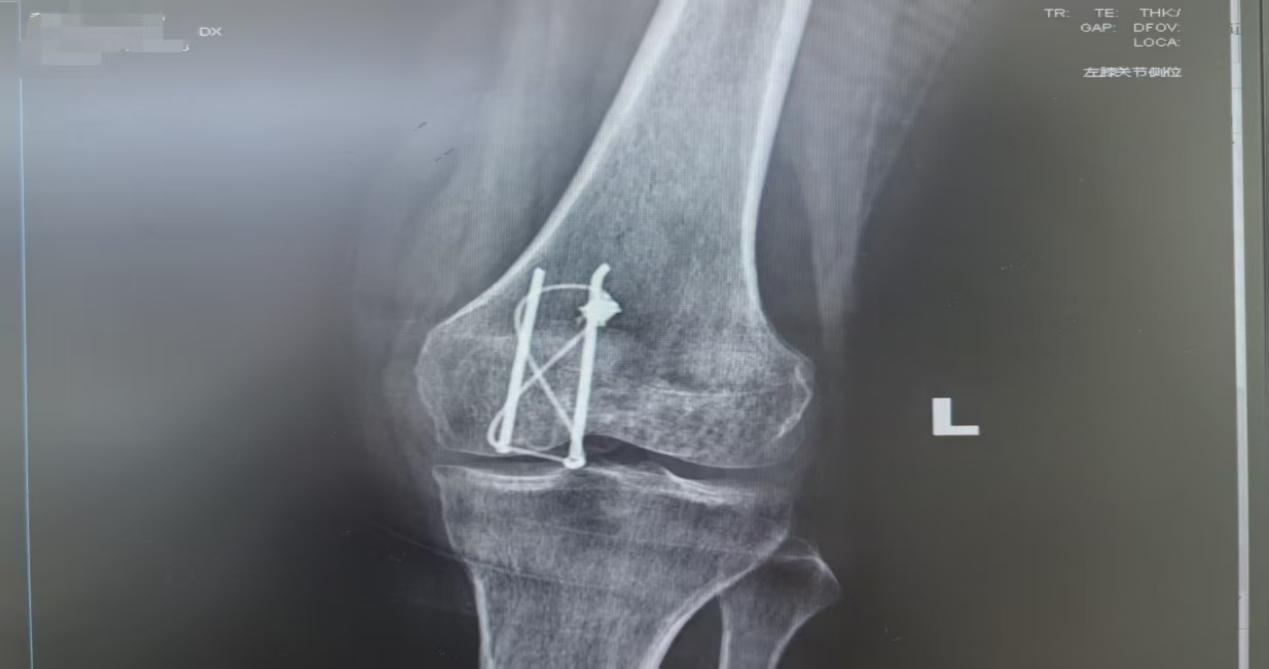

下图是髌骨骨折术后影像学左膝关节侧位片